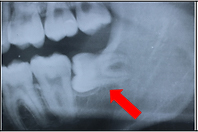

親知らずが生えていることが分かっている方は、一度歯科医院に行ってそのままにしておいてよいか診てもらいましょう。

下の写真は、親知らずが横向きに生えていて隙間があります。

下の写真は、その隙間に食べかすが入ってしまっています。

この隙間は下の方が深歯ブラシが届かず、このままでは親知らずと手前の歯が2本とも虫歯になってしまうので抜いたほうが良いケースです。